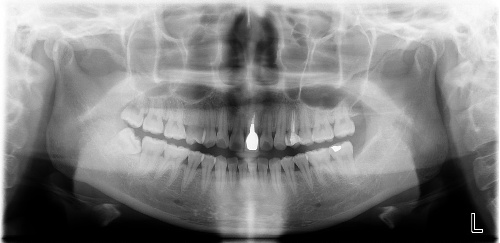

一般情况下,我们牙齿的蛀牙会经历这几个过程:大家看下图↓↓↓

一般情况下到了深龋,并伴有疼痛,说明蛀牙已经影响到牙髓腔了,如果牙髓被感染了就要进行根管治疗。并不是医生想要唬你。如果还没到达深龋,没有感染牙神经,一般只需要进行去腐后常规补牙即可。